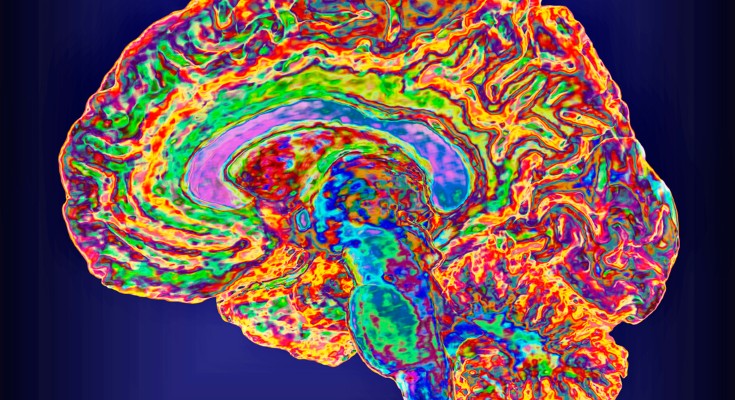

Whether cell types in the brain have been conserved during evolution is not clear. A comparison of the molecular recipes that define brain cell types in humans and mice reveals similarities and differences between species.

• Matthew G. Keefe

•  & Tomasz J. Nowakowski

The brain

Sam Falconer

The human brain isn’t much to look at. In the hand, it is a jelly-like mass, easily deformed by touch. But its unassuming appearance belies complex inner workings, many of which are still a mystery to scientists.